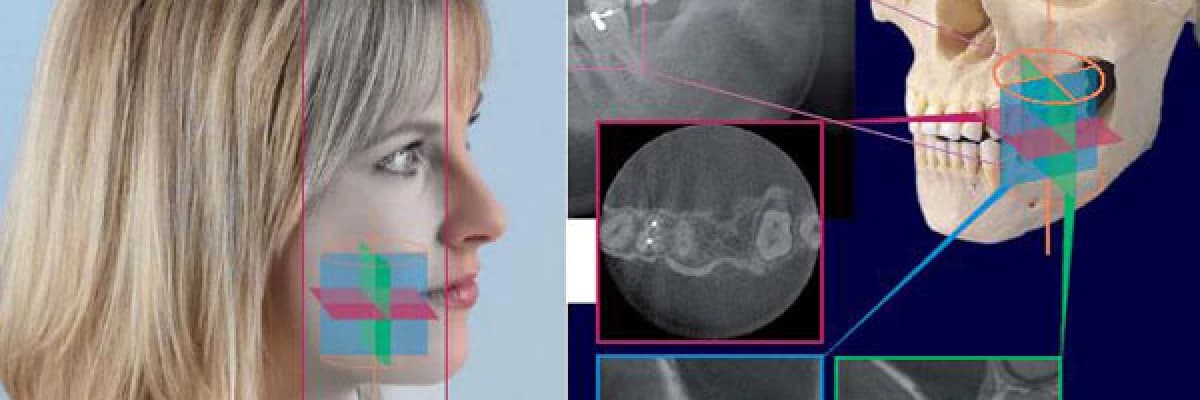

Dental tomografi x-ışını kullanılarak incelenmek istenilen bölgenin kesitsel görüntüsünü oluşturmaya yönelik radyolojik teşhis yöntemidir. Tomografi görüntüsü ile normal röntgen filmlerinde görülmeyen kemik ve yumuşak doku detayları görülebilmektedir. Merkezimizde konik ışın prensibi ile çalışan Morita marka INSTRUMENTARIUM OP300 3D cihazı kullanılmaktadır. Dental tomografi cihazı ile aksiyel, sagital ve koronal planlardan çok sayıda kesit alınır. Daha sonra bu kesitler ileri düzey yazılımlar yolu ile yeniden dilimlenip yapılandırılarak hedeflenen bölgenin istenilen açıdan ve her yönden görüntülenebilmesi sağlanır. Yüksek teşhis detayı ve ölçüm doğruluğu veren bu kesitler her türlü tedavide bir yol gösterici olmaktadır. Ayrıca kafatasının hacimsel görüntüsü oluşturularak kemik yapısı da incelenebilmektedir.

•Çekilen görüntüden koronal, aksiyal, sagital (cross section) kesitler alıp daha detaylı teşhis yapabilirsiniz.

•Volume rendering: 3 Boyutlu kafatası yapısı ve kemikler görüntülenebilir.